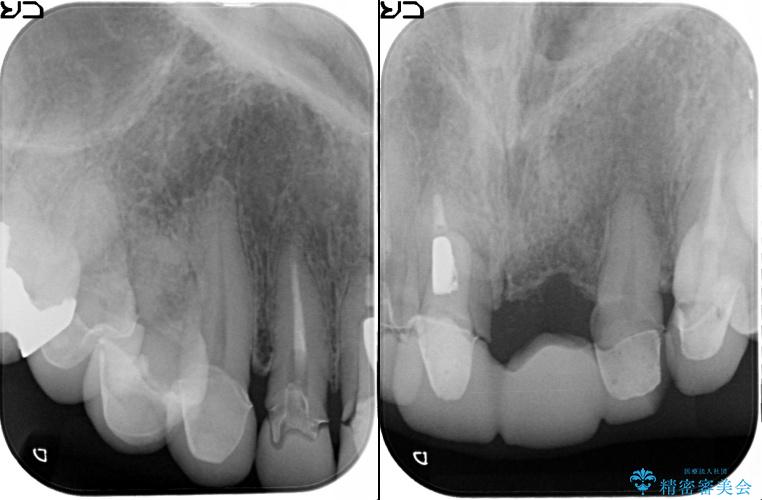

[ セラミック治療 ] 歯ぐきの際の黒ずみを改善したい

- 歯ぐきとセラミックの間の黒ずみが目立つので、きれいに治してほしい。と希望され来院されました。

歯ぐきの位置が変化しクラウン下の歯が見えるようになってしまったことで、審美障害が生じている状態です。

クラウンマージンの再設定を行うことで、黒ずんだ部分を再度覆い、審美障害を改善します。

歯ぐきの位置の経年的な変化は、誰にでも起きうる変化です。

強いブラッシングや電動歯ブラシの当て過ぎなども原因の一因となることがあります。